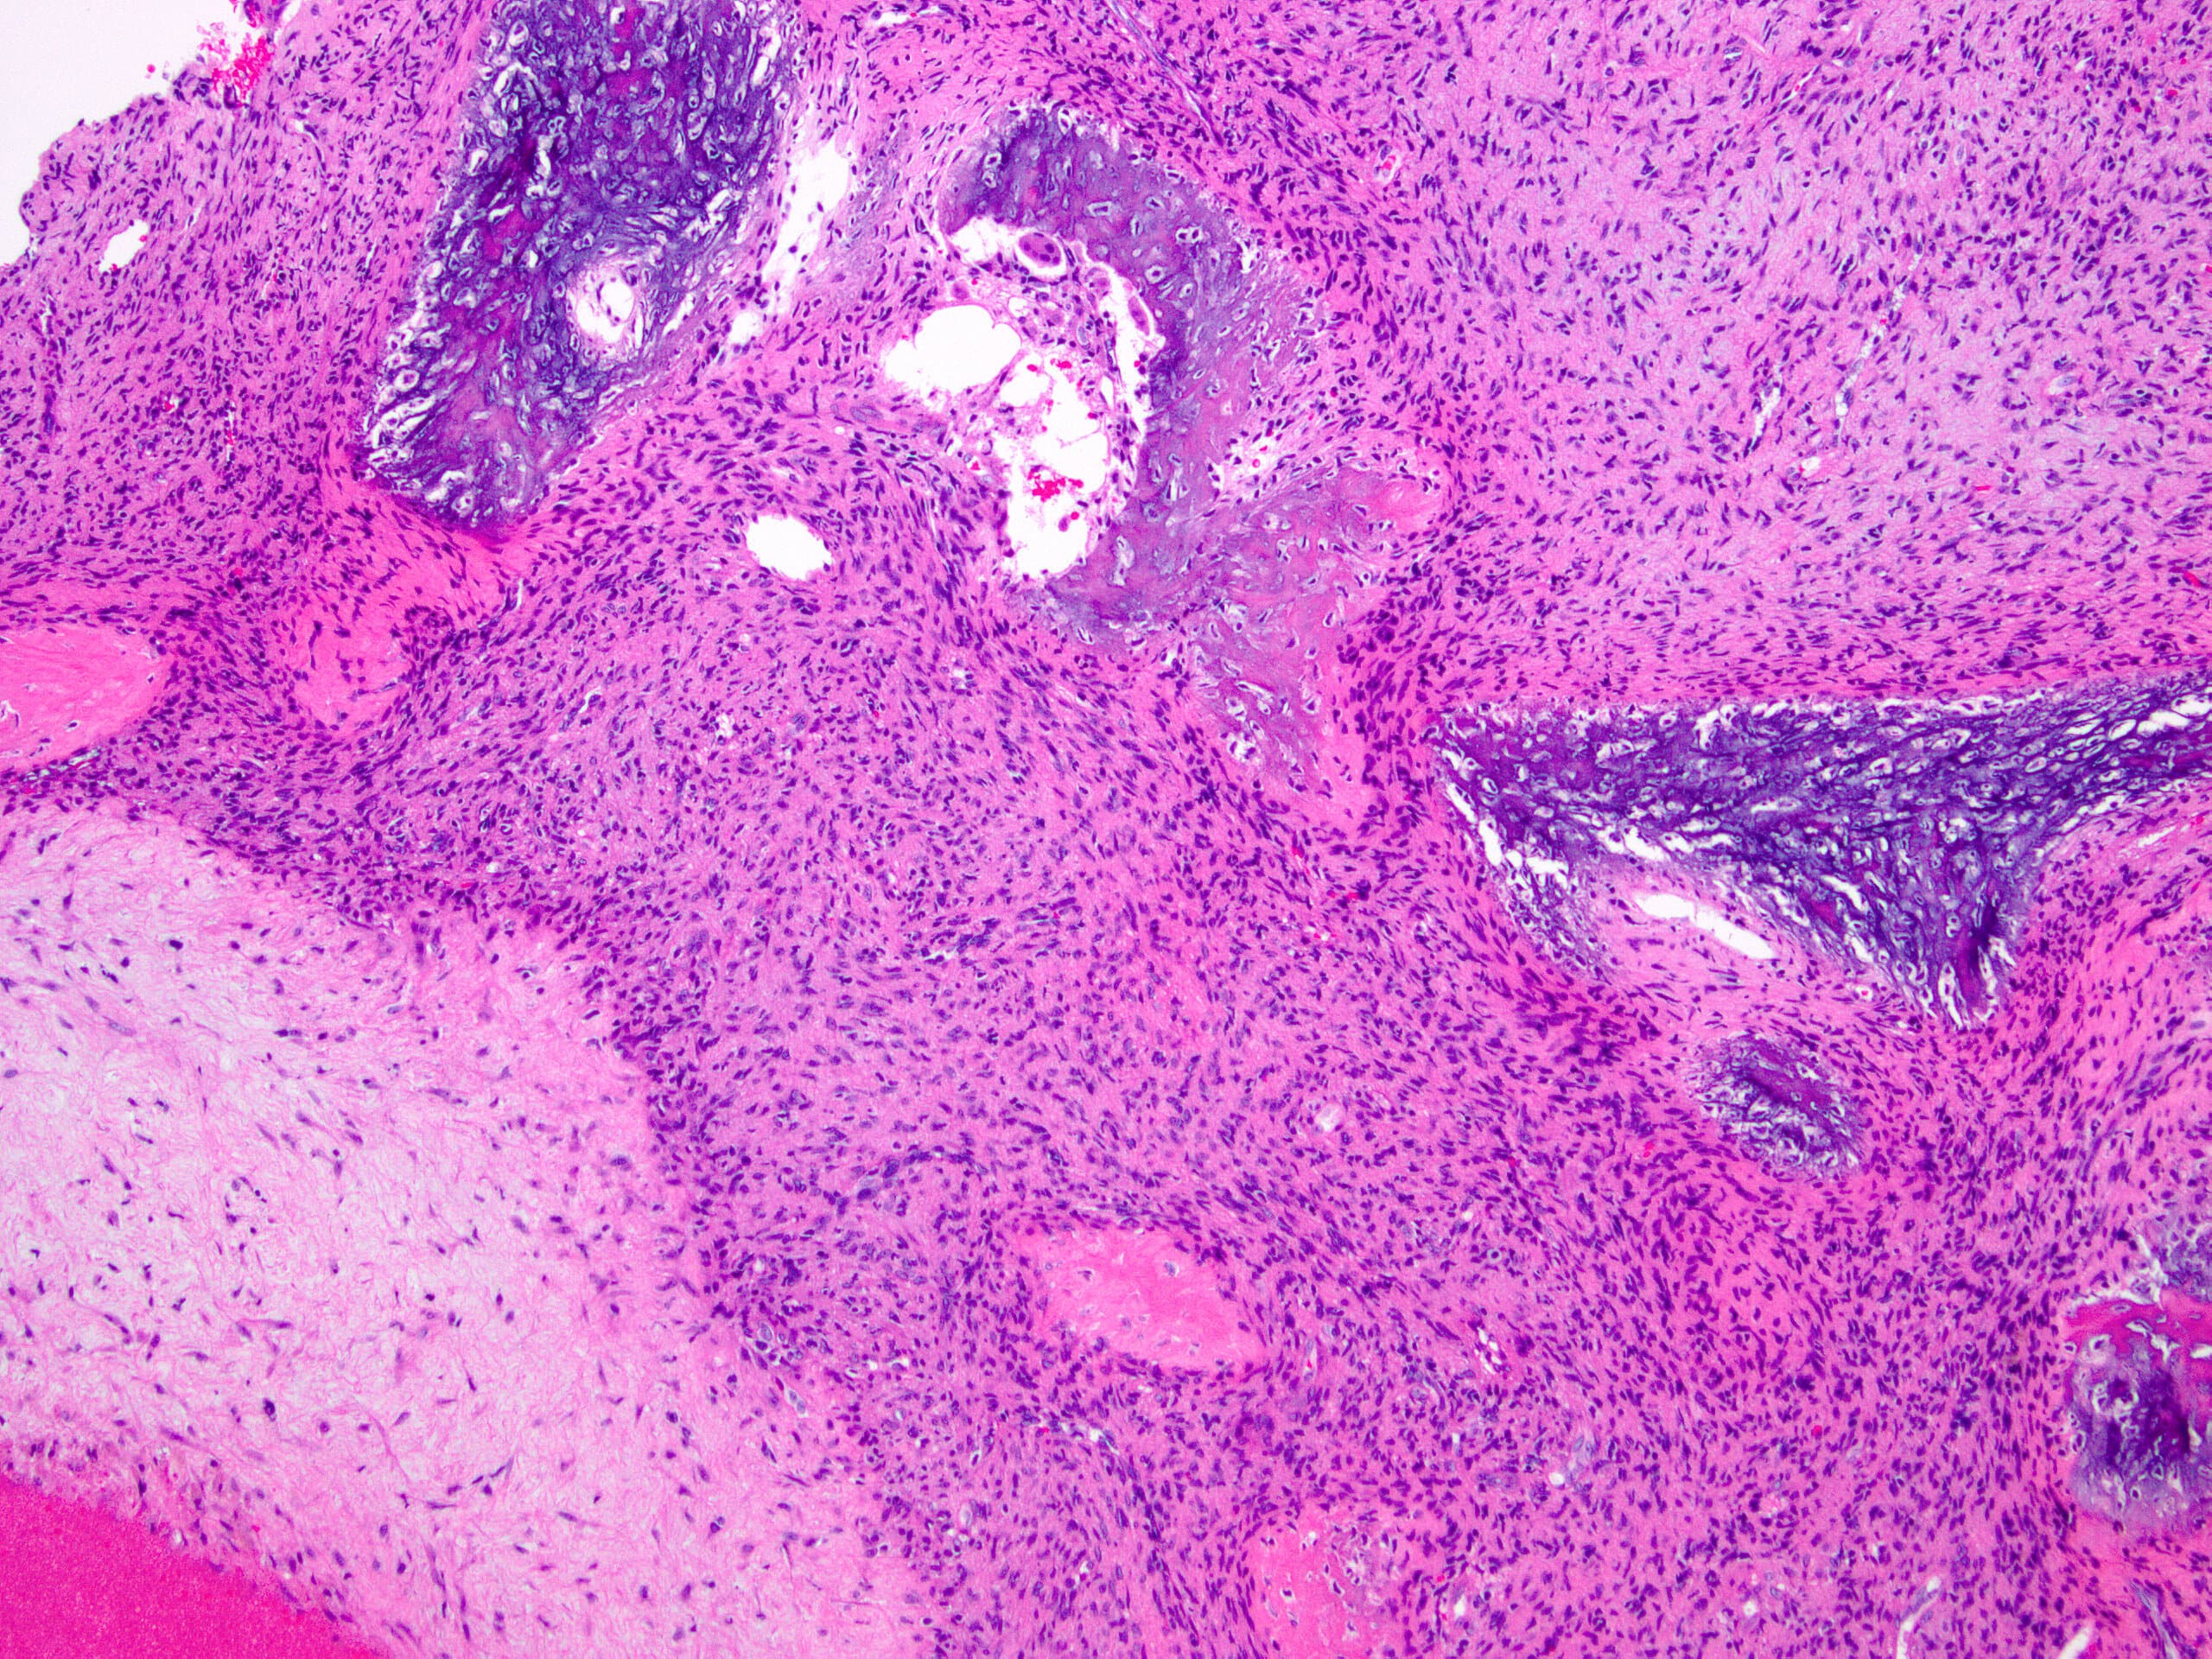

- Multiloculated cystic lesion

- Blood filled cystic spaces separated by cellular septa containing fibroblasts, giant cells and woven bone

- Calcified, basophilic material (blue reticulated chondroid-like material)

- Necrosis not common but mitotic activity is easily identified

- No cytologic atypia (Am J Clin Pathol 2015;143:823)

- Numerous giant cells in connective tissue that line large sinusoidal spaces

Microscopic (histologic) images

Contributed by Elham Nasri, M.D. and Kelly Magliocca, D.D.S., M.P.H.

A. Aneurysmal bone cyst. The H&E shows cystic spaces with stromal giant cells. Rearrangement of USP6 gene confirms the diagnosis in the above clinical and radiographic context.